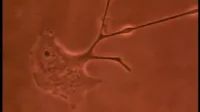

Фільм , що розкриває таємниці розвитку ембріона в утробі матері. На прикладі маленької дівчинки слідкуйте за дивовижним процесом розвитку людини протягом 9 місяців - від запліднення яйцеклітини до народження.